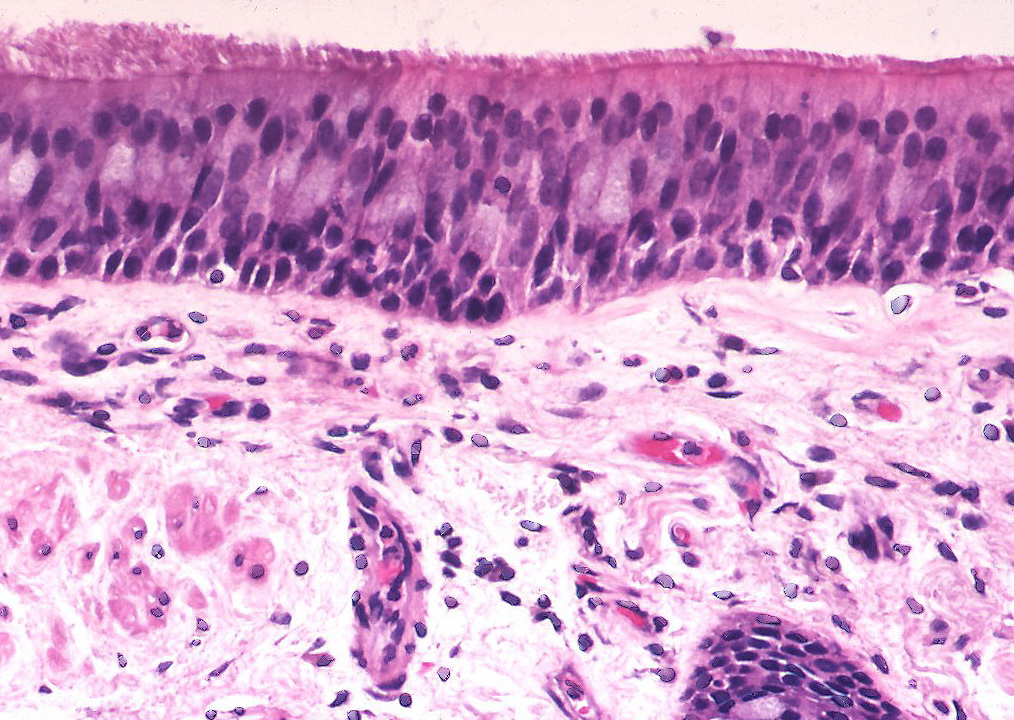

- Lungan, en del av endodermet

- Epitelceller!

- Cilier

- Transporterar skräp till svalget.

- Skräpet sväljs ner.